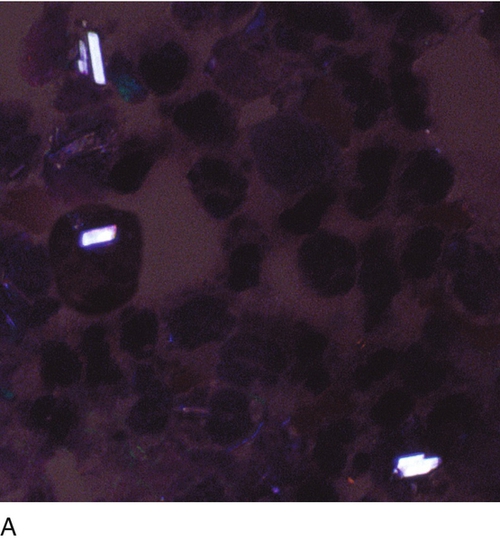

Each evaluation of synovial fluid should include a careful examination for crystals. Although it is not necessary to use a stain, Wright stain is sometimes used. A polarizing microscope with a red compensator should always be used for confirmation. The most common crystals are monosodium urate, calcium pyrophosphate dihydrate, and cholesterol.

Gout

Notice the orientation of the crystals and corresponding colors. Crystals appear yellow when parallel to the axis of slow vibration and blue when perpendicular to the axis.